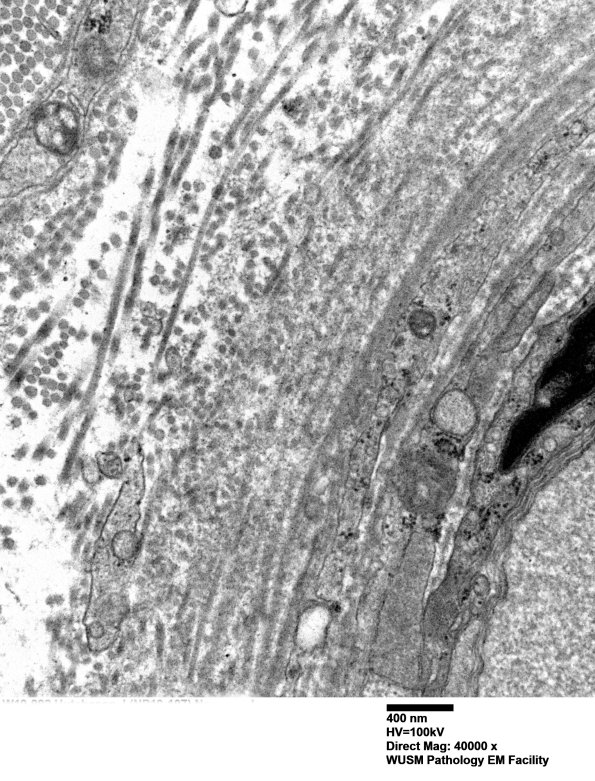

Multiple magnifications of a mildly enlarged vessel which has been expanded by collagen deposition. (electron micrographs)